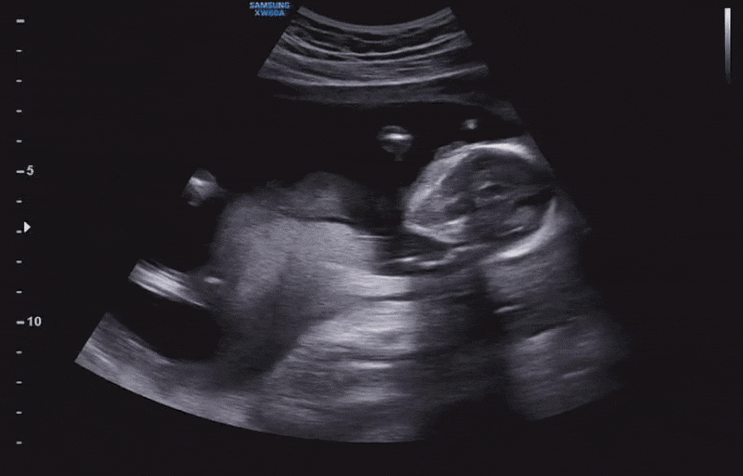

21주 2일 : 정밀초음파, 입체초음파, 열달후에 수치, 복부둘레 큰/작은 아기

21주차에는 정밀초음파가 있었어요. 제가 다니는 병원은 이렇게 정밀 초음파를 책자로 만들어서 주셨어요. ...